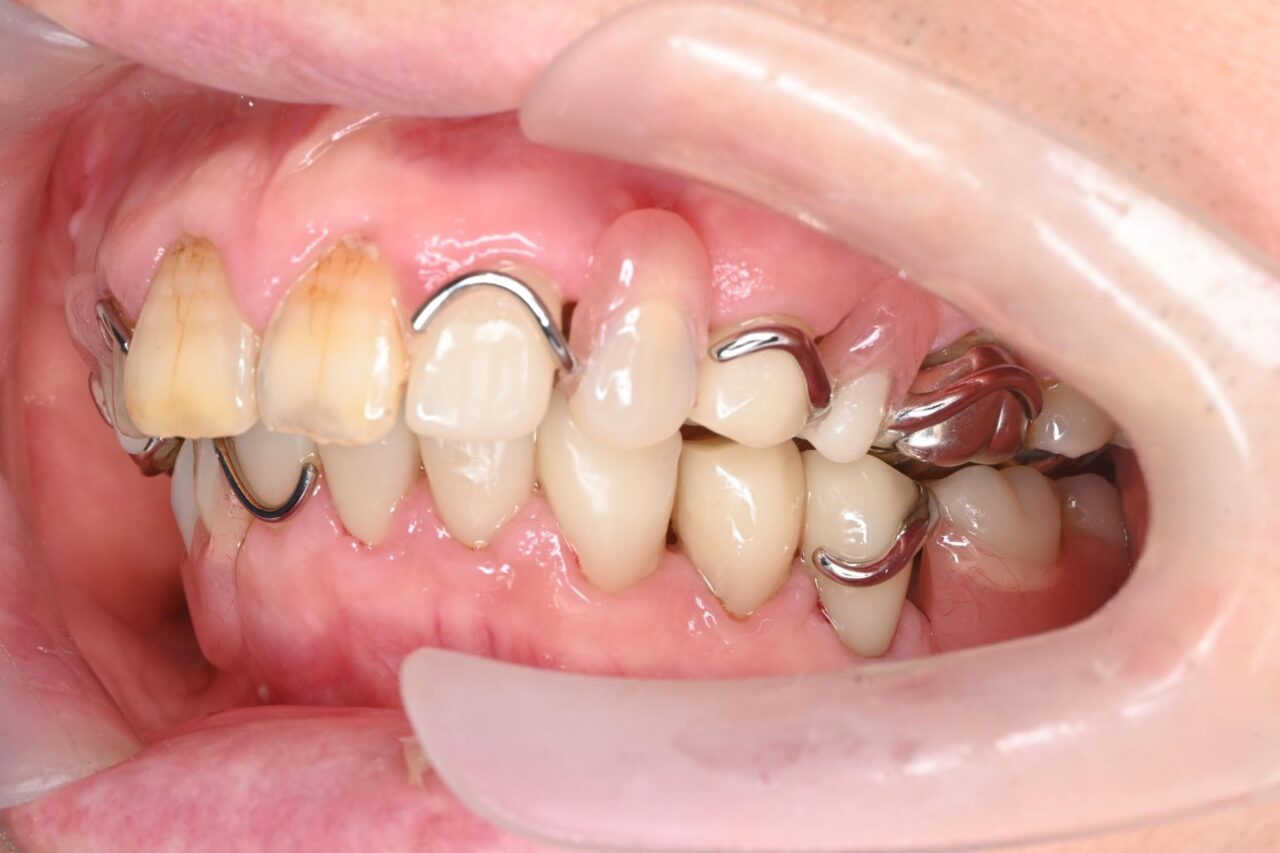

左側

一見、左側は歯があるように見えますが、ブリッジが入っていてかぶせ物の中が完全に虫歯でやられてしまっています。(レントゲン写真で確認済み)

歯科治療において、ブリッジは絶対にやってはいけません!!!!!!!